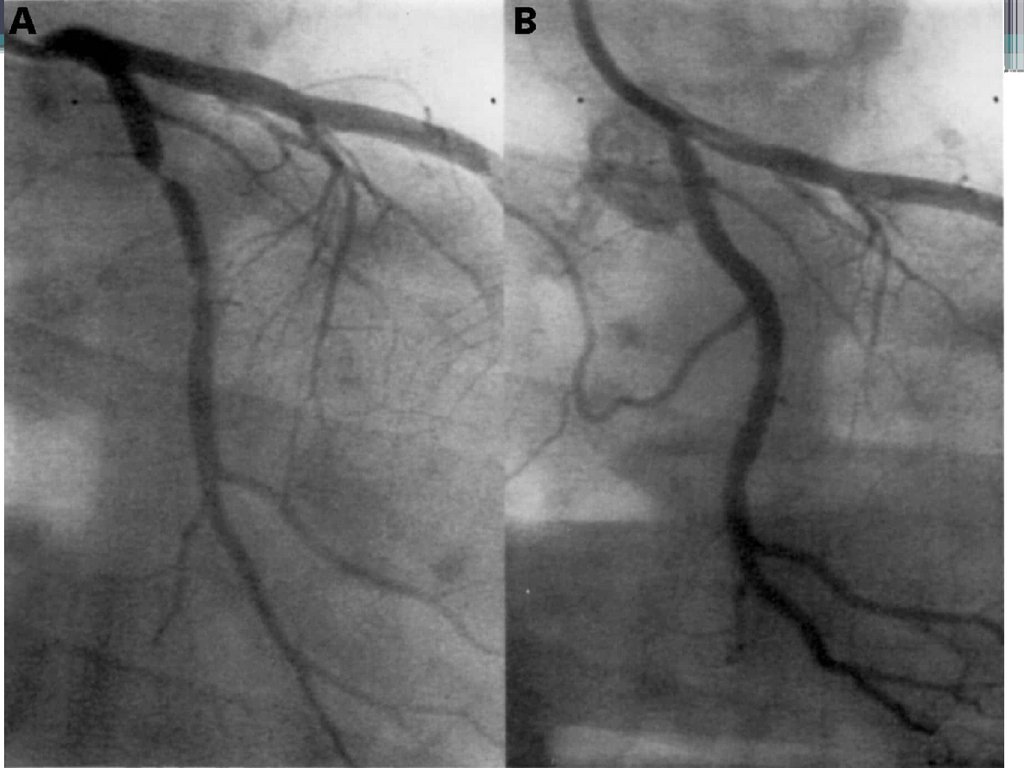

ОКС с подъемом сегмента ST

Подъем сегмента ST свидетельствует о наличии

трансмурального

(субэпикардиального)

повреждения

миокарда

Развитие вышеуказанных изменений возможно только в

случае

сосуда

тотальной

окклюзии

крупного

магистрального

Тотальная окклюзия ПМЖВ